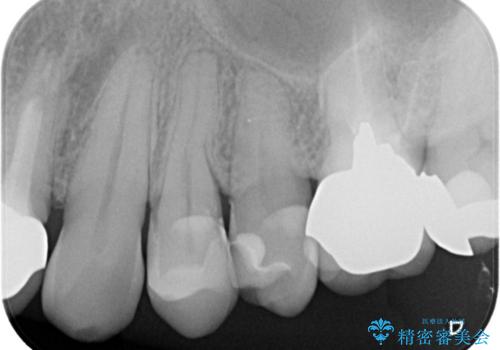

- 奥歯の被せ物が欠けたを主訴に来院された患者様です。欠けてしまった被せ物を除去後セラミックインレーで治療を行いました。

欠けた範囲が大きく被せ物を外して後、セラミックインレーで治療を行いました。欠けたままの状態を放置しているとそこに食べ物が詰まり虫歯になってしまうので早めの治療が必要です。